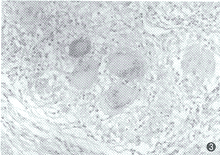

抗胰蛋白酶缺乏症免疫螢光法和免疫細胞學示沉積包涵體為α1-AT,此包含物在純合子也可看到。此類包涵物的密度和範圍與有無肝病表現似無確切關係,但無該包涵體沉積則無肝病發生,說明該包涵體在該病發病機制中可能起一定作用。

電鏡下可見肝細胞內擴張的粗面內質網內含特徵的形態不一的沉積物,而高爾基體內則無此沉積物,沉積物的量個體差異很大,膽管細胞內也可見到。另外,肝細胞內還可見糖原、空泡、脂褐素及膽汁淤積。